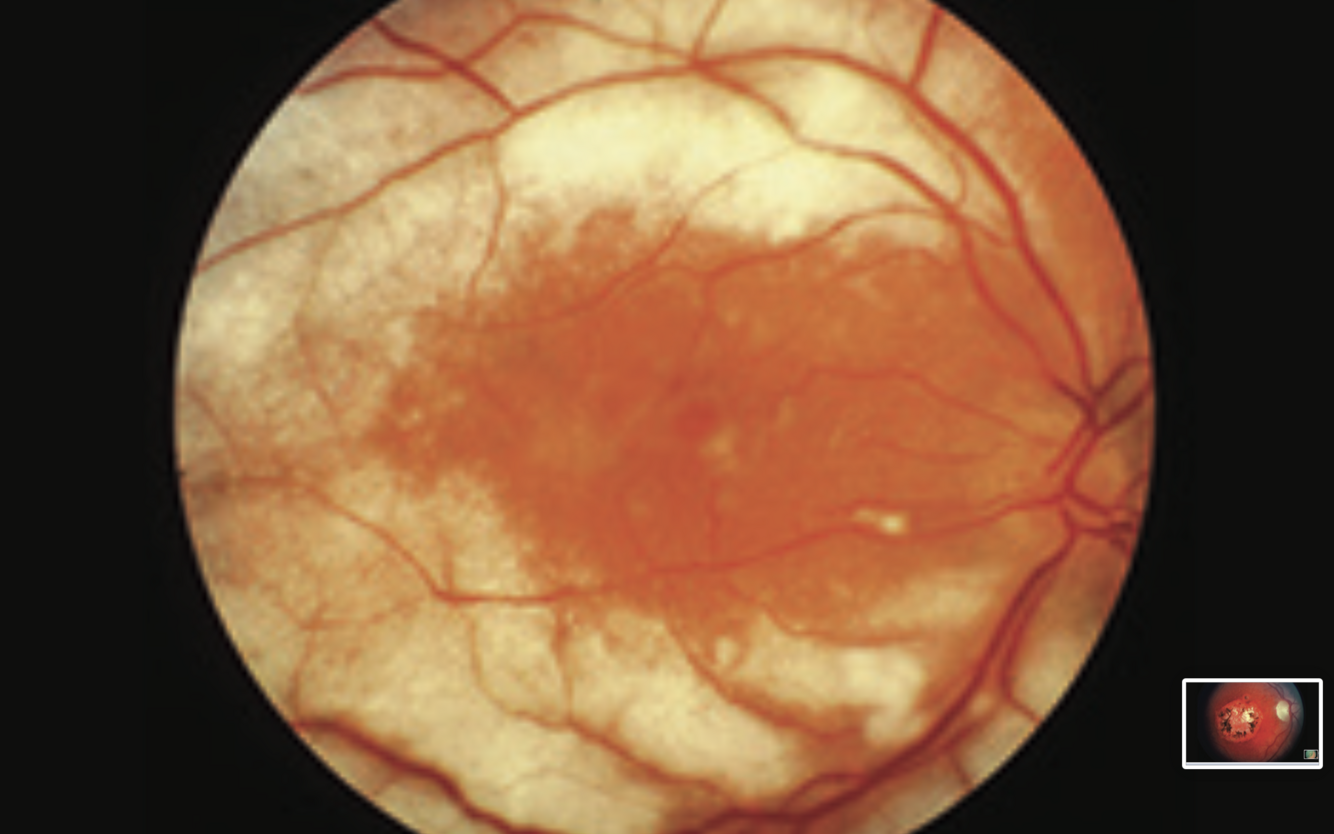

Diabetic Maculopathy

- hard exudates in macular area

- flame haemorrhages and microaneurysms